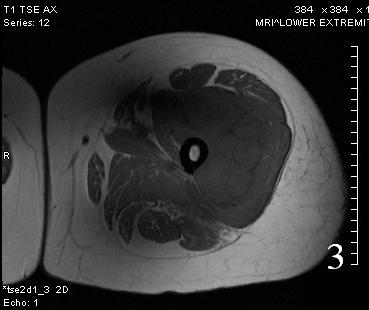

MRI

• Low to intermediate signal intensity on T1W

• High signal intensity on T2W

• Usually heterogeneous from necrosis and hemorrhage

Fig. 3

Fig. 4

Fig. 3-4 Axial (Fig. 3) and coronal (Fig. 4) T1 W MRI of the thigh shows an Extraskeletal Ewing Sarcoma that is iso-intense with the adjacent musculature.